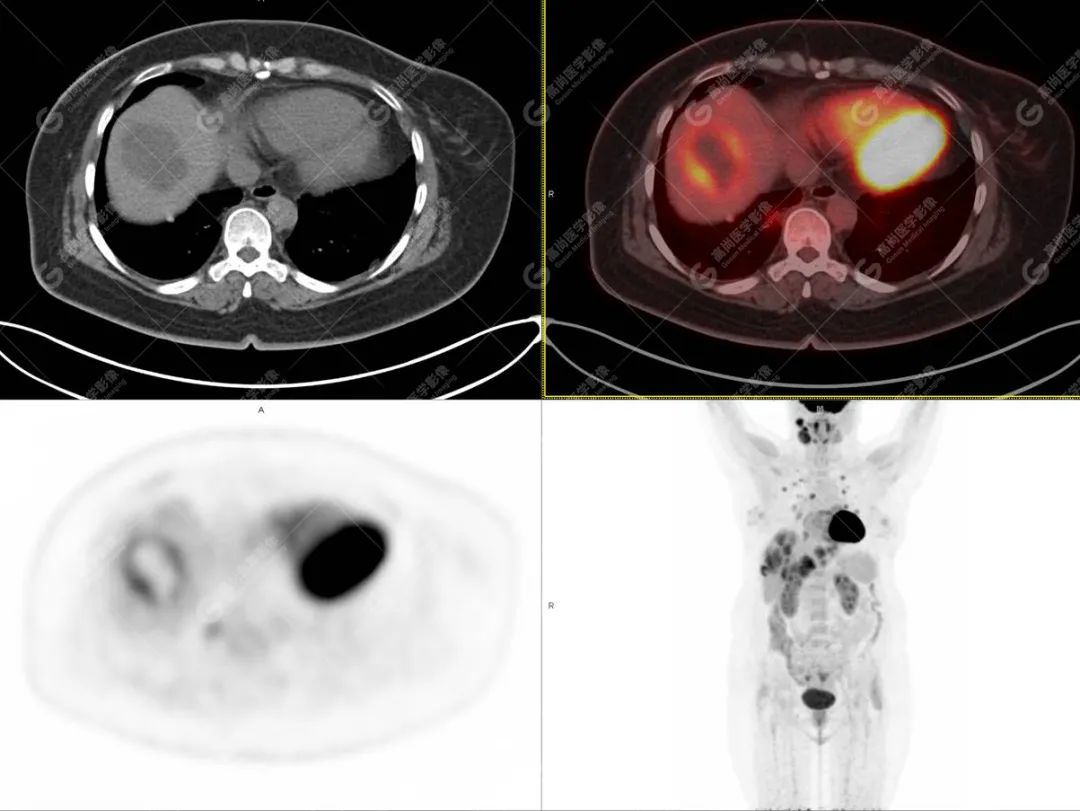

影像诊断:1. 结合病史,右颈部神经鞘瘤(低度恶性)术后改变,右侧颈部稍低密度及等密度结节,代谢异常增高,考虑为肿瘤复发并右颈部淋巴结转移,建议活检。 2. 双侧肺门及纵隔(4R 区)多发肿大淋巴结,代谢异常增高,考虑为转移。 3. 双肺多发大小不等实性结节,部分代谢增高,考虑为转移。 4. 肝脏多发低密度结节及肿块,代谢异常增高,考虑为转移。 5. 右侧第 8 前肋骨骨质破坏,代谢异常增高,考虑为转移。